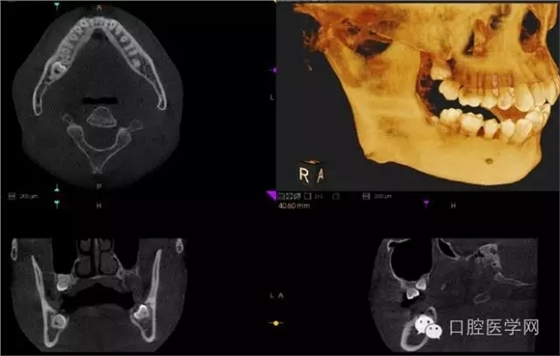

4.阻生牙

最常見于下頜第三磨牙

X線表現(xiàn):確定阻生牙的位置;確定阻生方向;牙根數(shù)目和形態(tài);阻生牙有無齲齒和根尖情況;與第二磨牙的關(guān)系;與下頜管的距離和磨牙后間隙的大小。